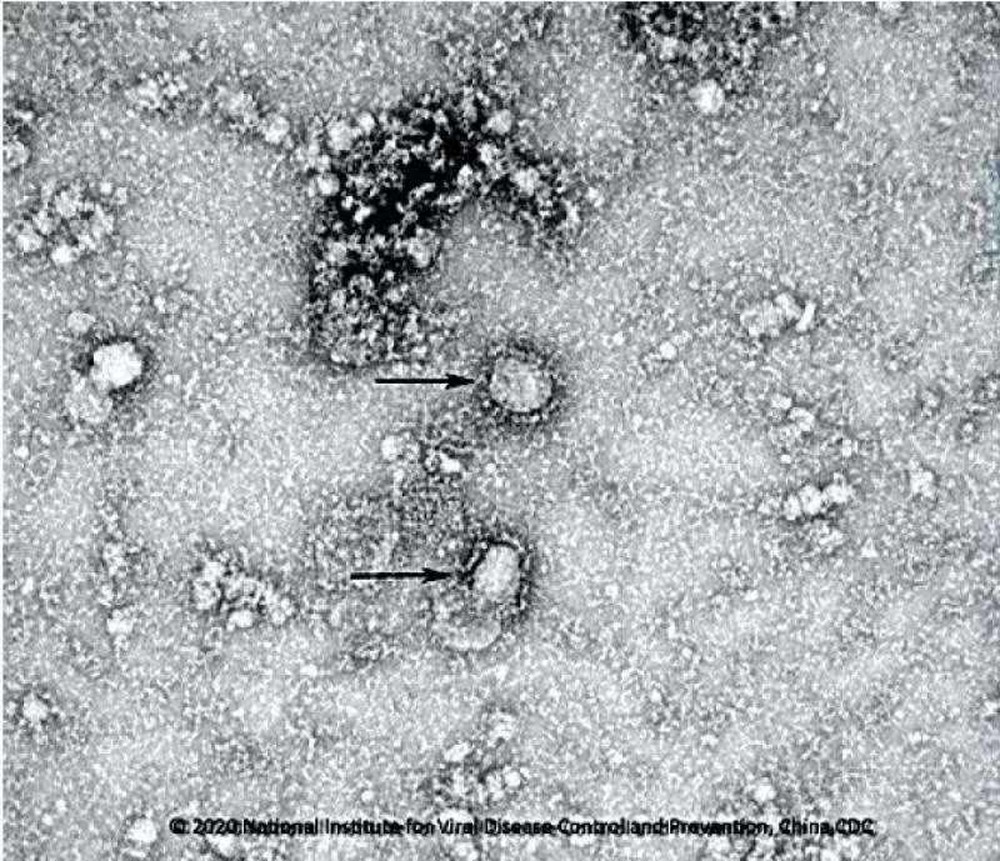

Quatorze pessoas infectadas com o novo coronavírus estão entre os mais de 300 americanos e parentes que foram retirados do navio cruzeiro “Diamond Princess” em quarentena no Japão para retornar de avião para os Estados Unidos.

O novo coronavírus já deixou quase 1.800 mortos e 70.500 pessoas infectadas na China. Outros cinco pacientes morreram fora da China.